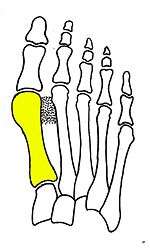

Syndesmosis procedure addresses specifically the two fundamental problems of metatarsus primus varus deformity that gives rise to the bunion deformity. They are leaning and instability of the first metatarsal bone . Syndesmosis procedure uprights the leaning first metatarsal bone with strong binding sutures between it and the second metatarsal bone (Fig. 2) and then also stabilizes it uniquely by creating a fibrous connecting bridge between these two bones (Fig. 3,4). First metatarsal bone can be readily realigned is because by definition of the metatarsus primus varus deformity its first metatarsal is abnormally loose and mobile.